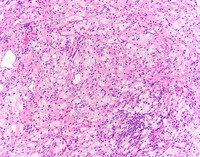

Erdheim-Chester Disease

Category: Macrophage/Histiocytic and dendritic cell Neoplasms and disorders (2015) > L group > Erdheim-Chester disease